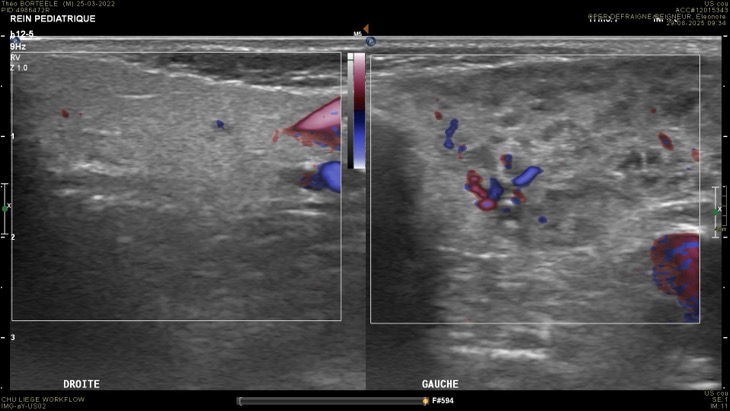

1. PAROTIDITE AIGUË

- Tuméfaction

- Nodules hypo (ganglions intra)

- Hypervascularisation